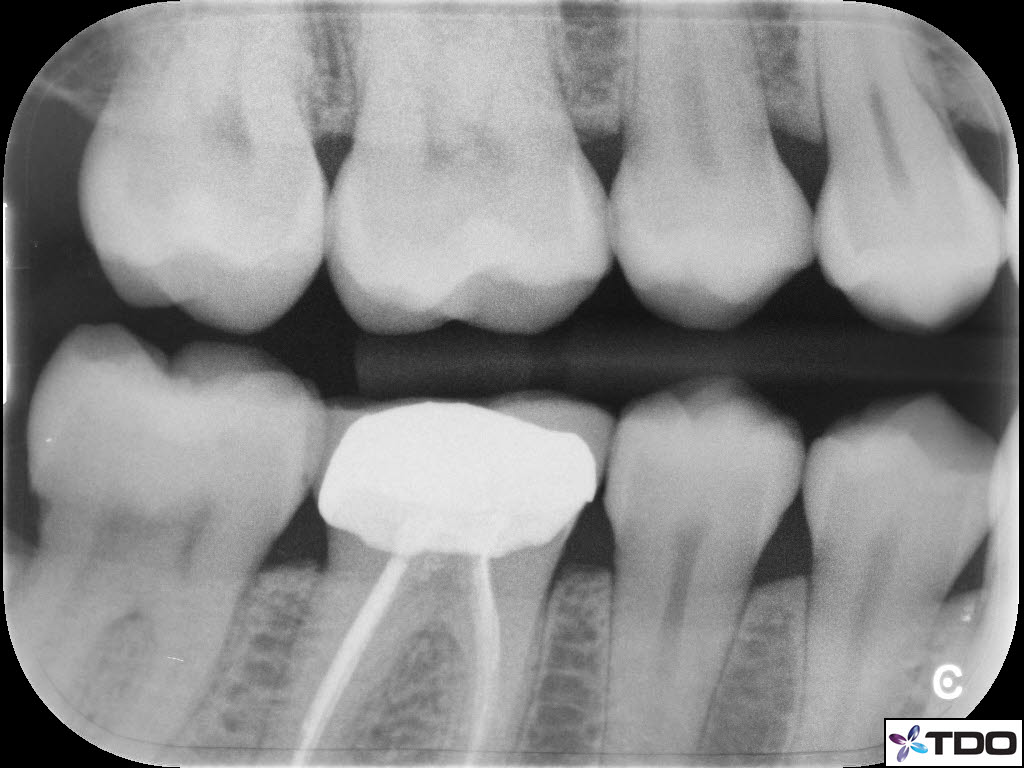

In the hierarchy of dentin conservation the existing restorative has the lowest priority and it quite frankly gets in the way of our access to the root canal system. But, after practicing directed dentin conservation for a while, you sometimes get lucky. The patient is 40yo. She was symptomatic at the time of treatment and interestingly the mesiobuccal canal was partially vital while the mesiolingual, distobuccal and distolingual canals were partially necrotic. She was asymptomatic at the completion visit as well as at the follow-up appointments.

Hi Gergely. The crown was less than two weeks old when the patient was first seen in my office. The previous crown was 15 yrs old and was seldom sensitive; the RD replaced the crown due to an “open margin.” Heat/cold sensitivity ensued after the crown prep. Four days after the permanent crown was cemented the patient woke up with severe throbbing pain and the temp sensitivity became worse. When she presented to my office she reported severe biting tenderness and tender submandibular lymph nodes.